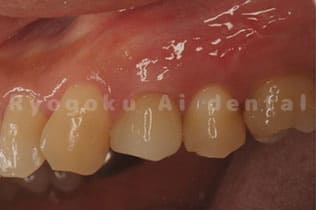

Case07

-

- 原因

- 右下6番歯根破折

- 治療内容

- インプラント治療

- 治療費用

- 約600,000円

右下の腫れが治らないとの事でご来院された患者様です。歯が割れていたため、抜歯を行い、骨に代わるお薬を入れ、インプラントを埋入致しました。経過良好で大変満足していただけました。

<リスク・副作用>

治療後、痛みや違和感、出血、腫れなどが出る事があります。喫煙者、糖尿病などの方の場合、歯が生着しない場合があります。